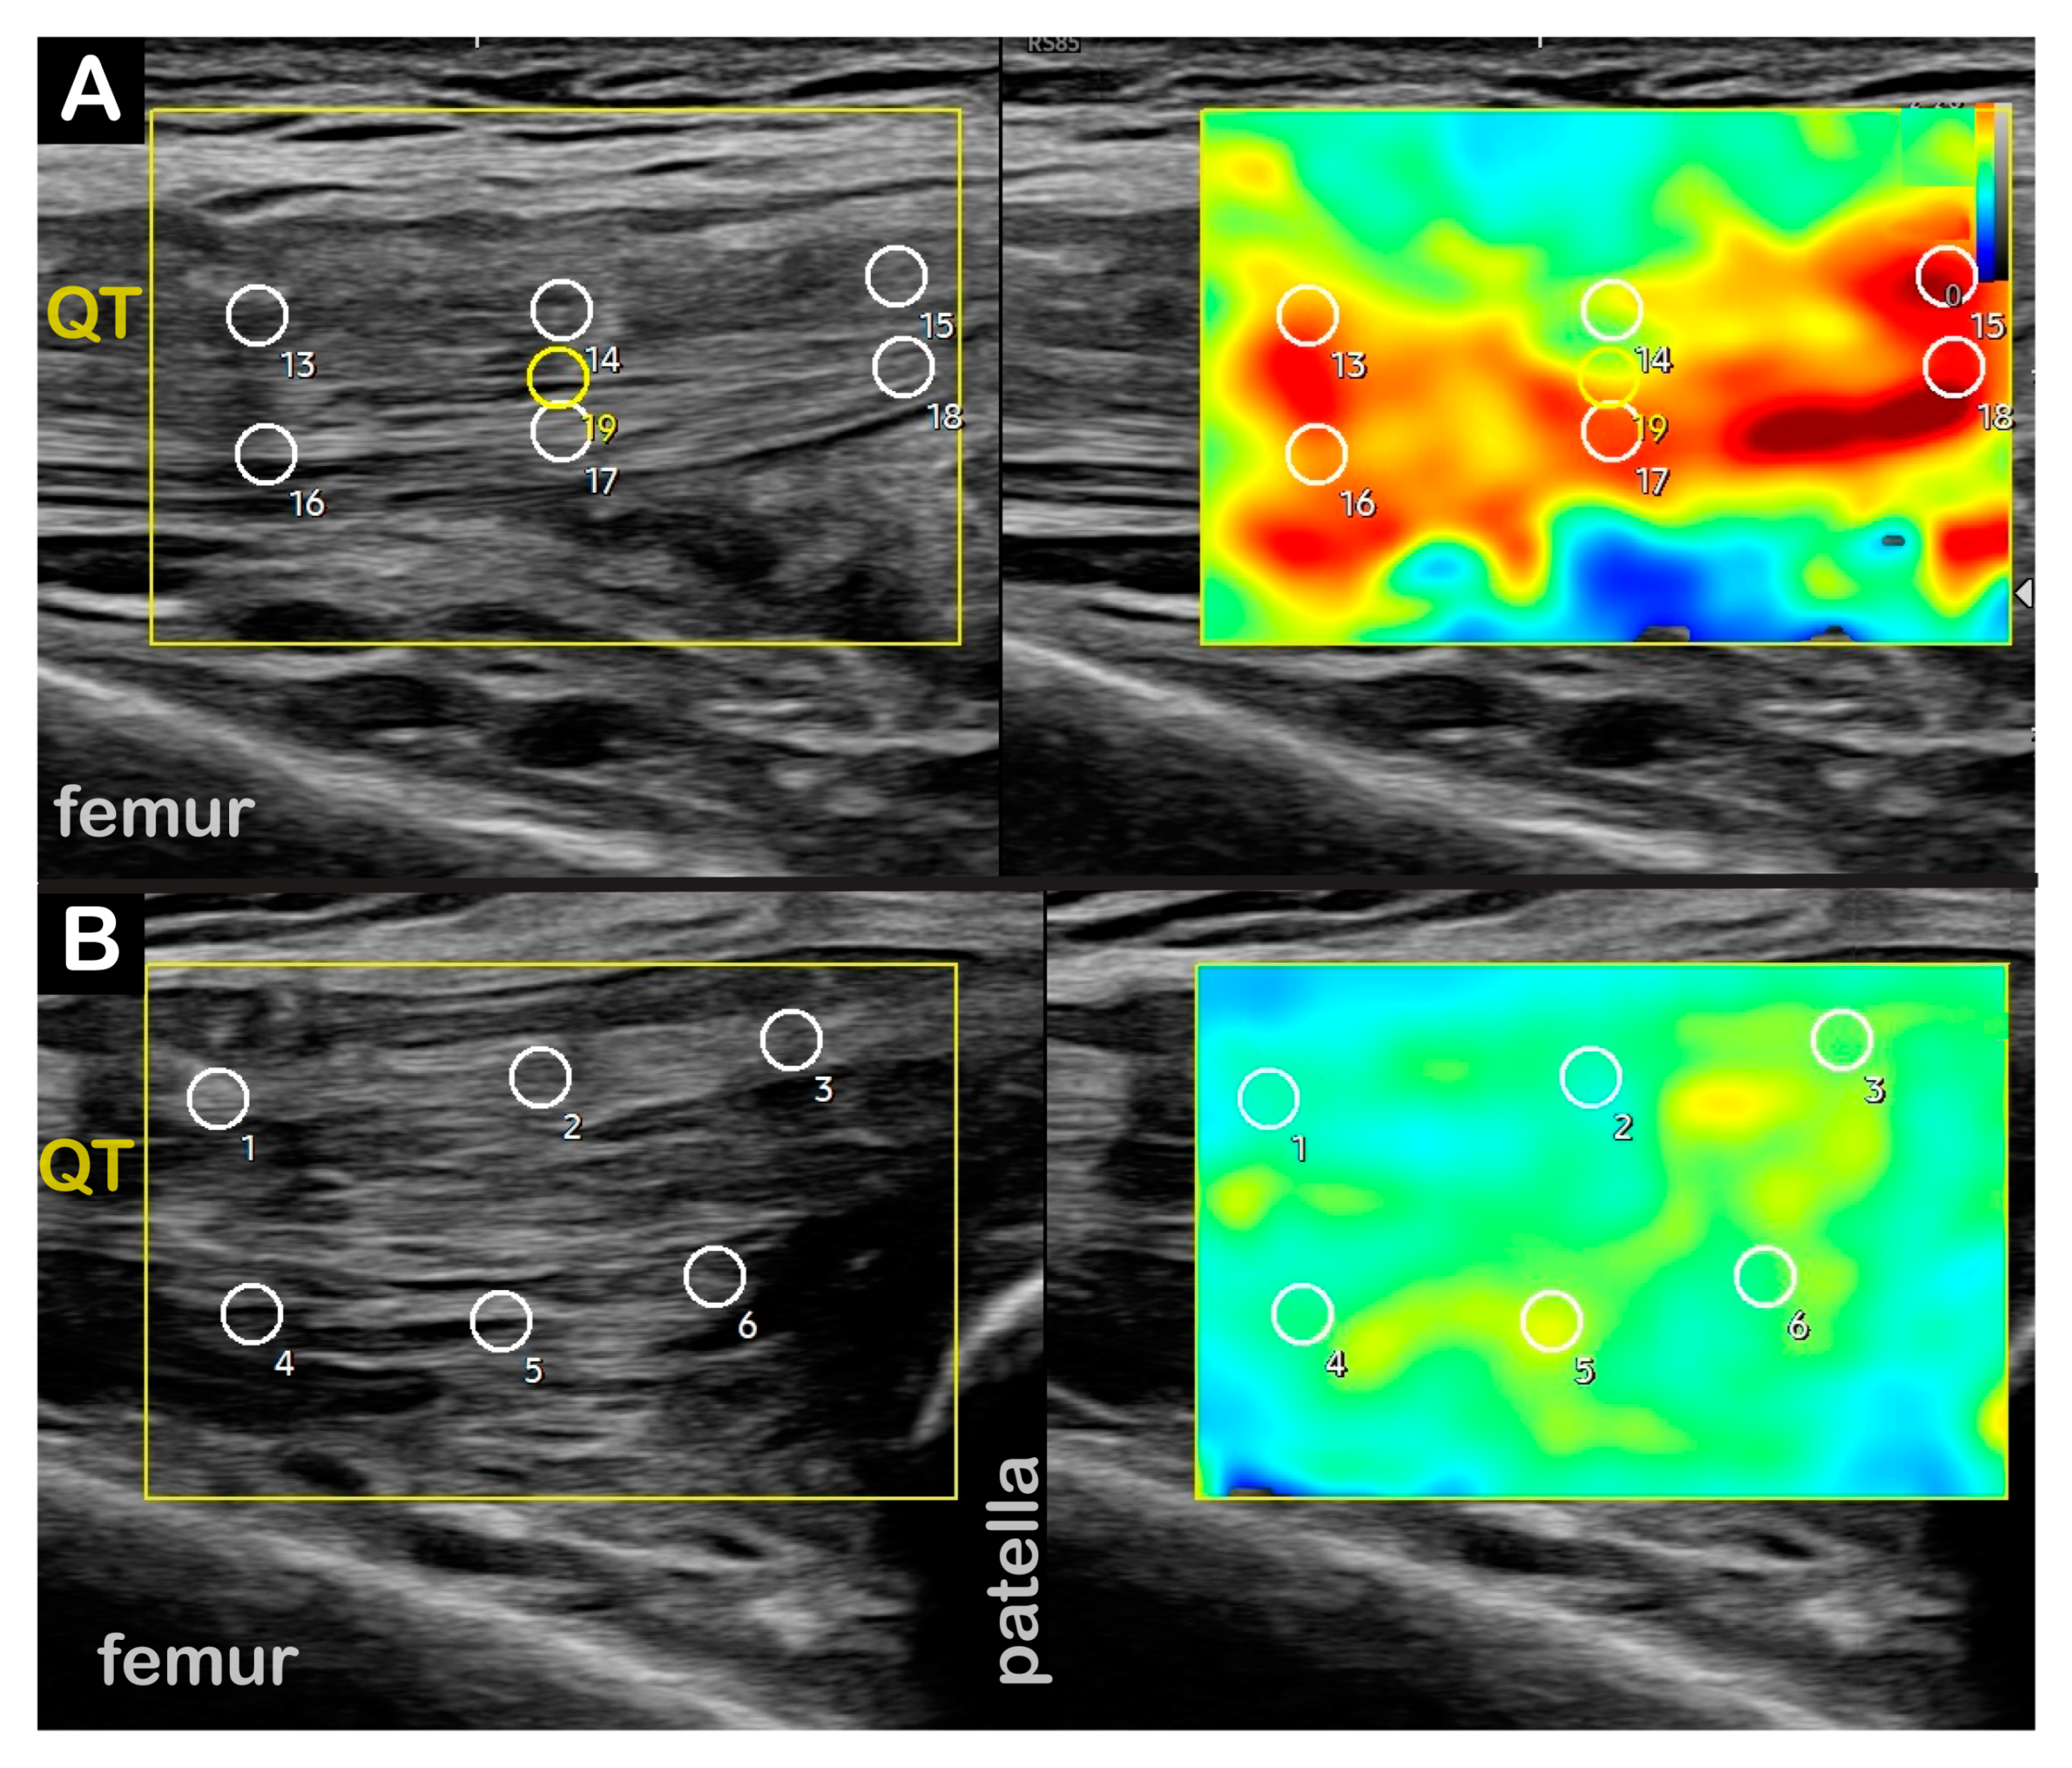

| Diagnostic US |

| Diagnostic US | |